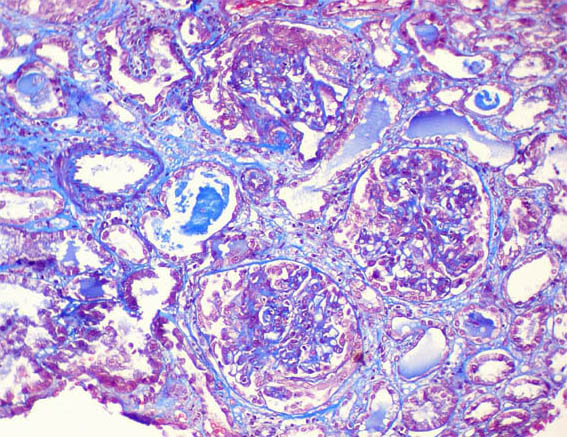

Figure 3. Masson's trichrome staining, X400.

Figure 4.Masson's trichrome staining, X400.